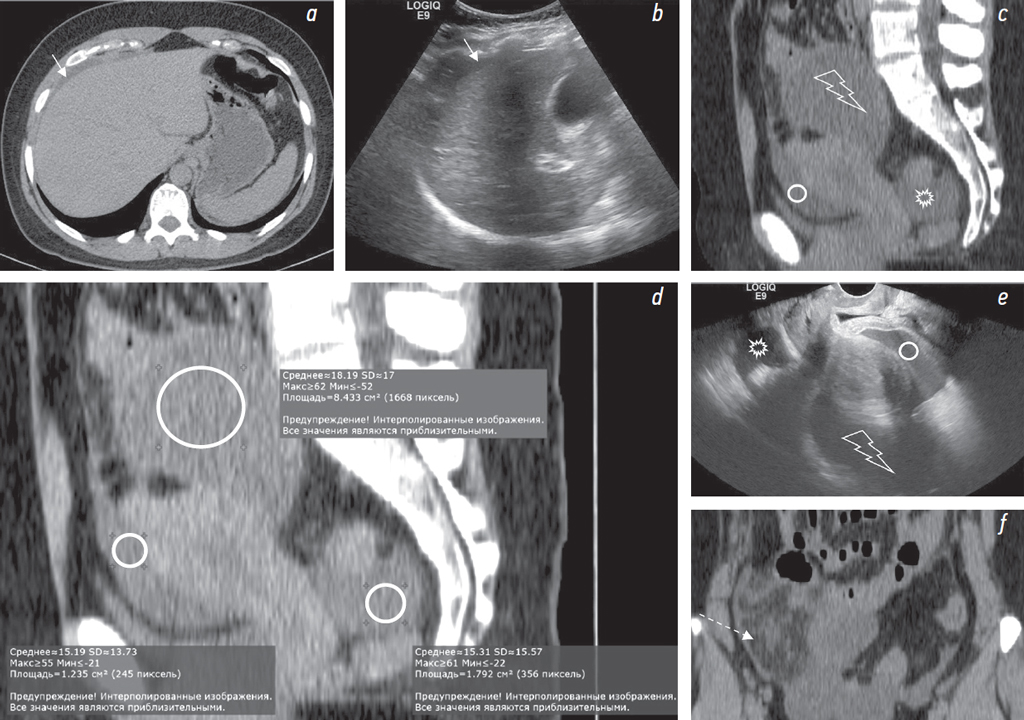

При КТ без внутривенного контрастирования выявлены свободная жидкость в полости таза, по боковым фланкам, около печени (рис. 1, а, c, d); в области правого яичника образование жидкостной плотности размерами до 77 × 67 мм (рис. 2, а), стенка неравномерной толщины, до 7 мм (рис. 3, а, b); инфильтрация большого сальника (рис. 1, f), остальные органы без особенностей. Заключение: КТ-признаки свободной жидкости в брюшной полости, образования правого яичника. При КТ грудной клетки не выявлены признаки неопластического или инфекционного процесса.

Рис. 1. На нативной КТ-томограмме в аксиальной плоскости (а) и на трансабдоминальной сонограмме (b) визуализируется свободная жидкость около печени (стрелка). На нативных КТ-томограммах в сагиттальной (c, d) плоскости и на трансвагинальной сонограмме (e) показана кровь в виде свободной жидкости в маточно-пузырном пространстве (круг) и в маточно-прямокишечном пространстве (звездочка). Эндометриоидная киста (молния) визуализируется на КТ-томограммах (c, d), трасвагинальной сонограмме (e). На КТ-томограмме (d) показаны коэффициенты ослабления рентгеновского излучения в единицах Хаунсфилда в эндометриоидной кисте и в свободной жидкости в полости малого таза. Инфильтрация большого сальника справа (пунктирная стрелка) на КТ-томограмме во фронтальной плоскости (f)

При УЗИ: свободная жидкость в брюшной полости (преимущественно около печени, в гепаторенальном кармане, в правом боковом канале толщиной слоя до 10 мм) и малом тазу (рис. 1, b, e). В области правых придатков определяется образование (размерами около 65 × 70 × 90 мм) с содержимым в виде мелкодисперсной эховзвеси («матовое стекло»), стенками неравномерной толщиной 7–10 мм с прилежащими по наружному контуру гипоэхогенными массами (сгустки?) (рис. 3, c). В околоматочном пространстве эховзвесь в жидкости идентична содержимому кисты в яичнике (рис. 4, а, b). Матка и левый яичник (рис. 2, b) без эхоструктурных особенностей. Паренхиматозные органы брюшной полости и забрюшинного пространства без УЗ-признаков структурной патологии. Заключение: УЗ-признаки могут соответствовать гемоперитонеуму вследствие разрыва кисты правого яичника (вероятно, эндометриоидной).